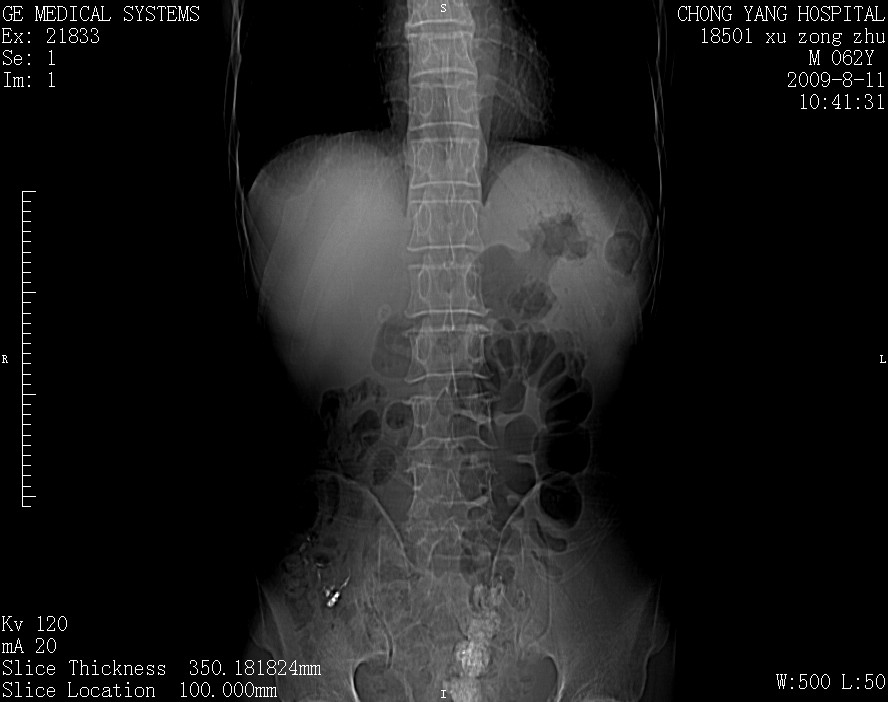

以下是引用杀毒软件在2009-8-11 16:35:00的发言:[br]肝内胆管扩张局限于左叶,胆管内有结石伴肝外胆管结石,胆管壁增厚呈弥漫性并发腹腔积液,胰腺边界模糊。[br][br]考虑---胆总管及肝内胆管结石继发胆管炎及胰腺炎,左肾下极囊肿,腹水。

以下是引用zjzjr在2009-8-11 17:35:00的发言:[br]肝内胆管扩张局限于左叶,胆管内有结石伴肝外胆管结石,胆管壁增厚呈弥漫性并发腹腔积液。[br][br]考虑---胆总管及肝内胆管结石继发胆管炎,左肾下极囊肿,腹水。